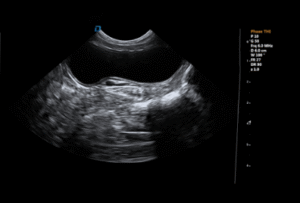

Veterinary ultrasound addresses this challenge directly in daily clinical practice. By allowing clinicians to visualize organs, soft tissues, fluid accumulation, and blood flow in real time, ultrasound often becomes the first imaging modality to guide diagnosis—especially when physical examination and laboratory results are inconclusive.

→ Abdominal ultrasound to evaluate liver, intestines, pancreas, and free fluid

Veterinary ultrasound helps localize lesions, characterize organ changes, and differentiate between inflammatory, degenerative, and neoplastic conditions. This reduces diagnostic uncertainty and limits unnecessary empirical treatments.